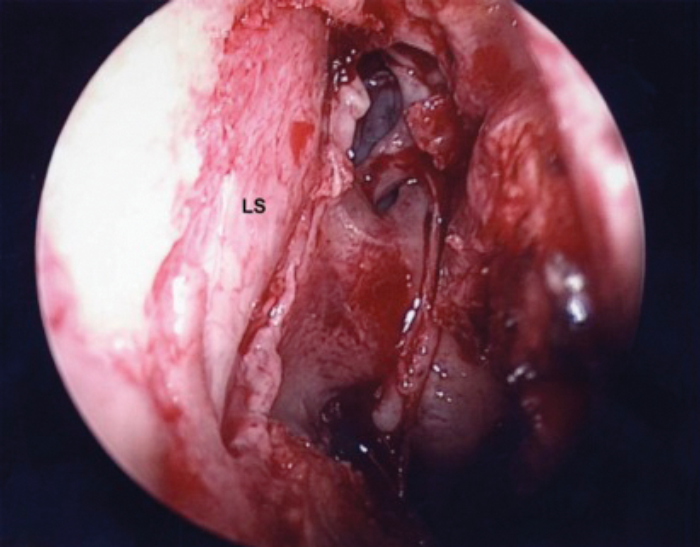

Once wide bone removal has been achieved, the sac should stand proud and exposed from just above the axilla of the middle turbinate down to the mid portion of the middle turbinate (Figure 4). The lacrimal puncta is dilated with a lacrimal punctum dilator (Figure 5) and the lower canaliculus cannulated with a 0 Bowman canalicular lacrimal probe. The sac is thus made to tent medially. A vertical incision is made along the lacrimal sac using a sickle knife (Figure 6). Lacrimal sac is opened like a book with an anterior and posterior flap. Horizontal incisions are then placed superiorly and inferiorly in the posterior flap and the midportion of the posterior flap removed with Bellucci scissors (Storz, Germany).

LS - Lacrimal sac

Figure 4. Complete exposure of lacrimal sac.